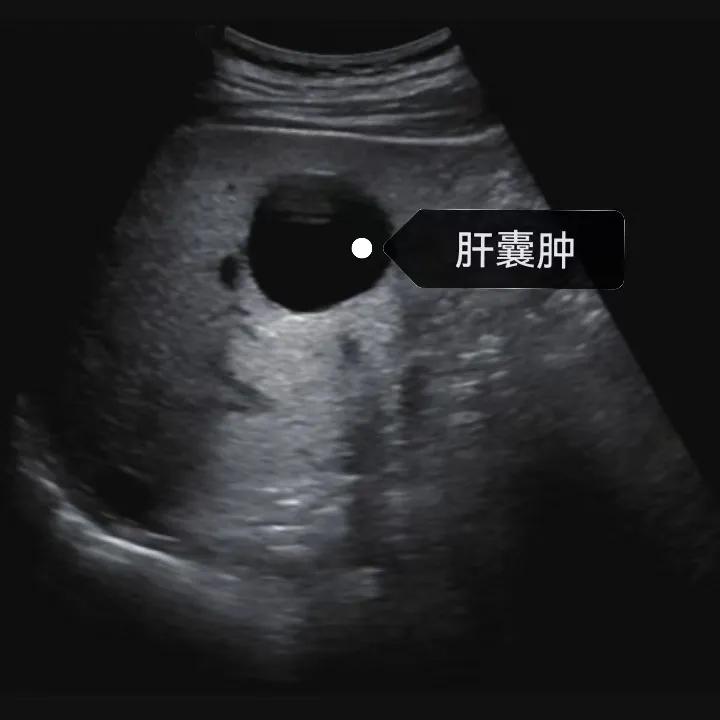

肝囊腫是一種常見的肝臟良性疾病,呈圓形或橢圓形,外由上皮細胞包裹形成包膜,內由清亮、無色、無細胞成分的囊液填充,看上去就像是一顆注滿了水的氣球,因此通俗一點說就是肝臟中的“水泡”。

超聲通常是診斷肝囊腫的首選方法,彩超對肝囊腫的檢出率可達98%,<1cm的囊腫也可檢出。肝囊腫常表現為圓形或橢圓形無回聲,包膜光滑完整,邊界清晰,可有側壁回聲失落征象,后方回聲增強。病程長、囊腫較大者或囊內有過出血、感染者,無回聲腔內可見少量絮狀回聲漂浮。超聲對肝囊腫的診斷準確而靈敏,且方法簡單、無創、費用低、可重復性高,因此常常被作為首選。